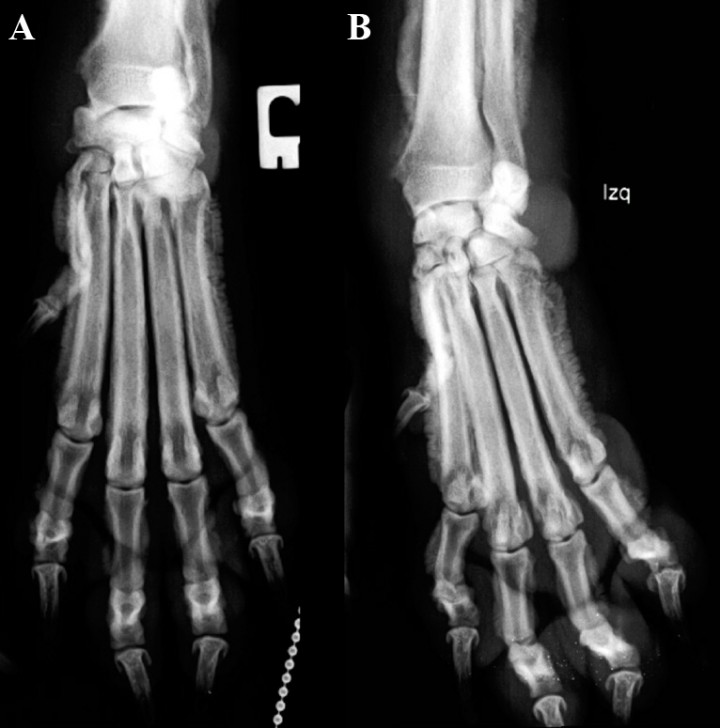

Se presenta un perro macho castrado de 5 años, Griffon Azul de Gascuña de 22 kg de peso. Acude a consulta por una cojera con inflamación de la extremidad anterior izquierda de 1 semana de evolución. En la exploración se observa dolor a la palpación de las extremidades anteriores con zonas de inflamación, sobre todo del tercio distal de las mismas. Las extremidades posteriores presentan también inflamación de la zona tarsal de forma más leve. Las alteraciones analíticas encontradas son neutrofilia leve (11,94 K/μl; valor de referencia: 2,95-11,64 K/μl), monocitosis (2,61 K/μl; valor de referencia: 0,16-1,12 K/μl), incremento de la ALP (296 U/l; valor de referencia: 23-212 U/l) e hiperglobulinemia (4,7 g/dl; valor de referencia: 2,5-4,5 g/dl). Se realizan radiografías digitales simples con proyecciones dorsopalmares (Fig. 1) y mediolaterales (Fig. 2) de extremidad anterior derecha e izquierda y proyecciones mediolaterales de la extremidad posterior derecha e izquierda (Fig. 3).

<p>Proyección dorsopalmar de la zona del carpo y metacarpo. <strong>(A)</strong> Derecha.<strong> (B) </strong>Izquierda. </p>

Proyección dorsopalmar de la zona del carpo y metacarpo. (A) Derecha. (B) Izquierda.

<p>Mismas radiografías de la Figura 1. Se observa reacción perióstica del tipo en empalizada (ver flechas) con afectación de la falange media de 2º dedo, en el aspecto lateral y medial de las falanges proximales (dedo I, II, III, IV, V), en el aspecto lateral del cuerpo del hueso metacarpiano I, II y V y del III y IV de forma más leve, y del tercio distal del cúbito y radio. No existe afectación de las superficies articulares ni destrucción ósea. Tumefacción de los tejidos blandos en la zona del carpo.</p>

Mismas radiografías de la Figura 1. Se observa reacción perióstica del tipo en empalizada (ver flechas) con afectación de la falange media de 2º dedo, en el aspecto lateral y medial de las falanges proximales (dedo I, II, III, IV, V), en el aspecto lateral del cuerpo del hueso metacarpiano I, II y V y del III y IV de forma más leve, y del tercio distal del cúbito y radio. No existe afectación de las superficies articulares ni destrucción ósea. Tumefacción de los tejidos blandos en la zona del carpo.